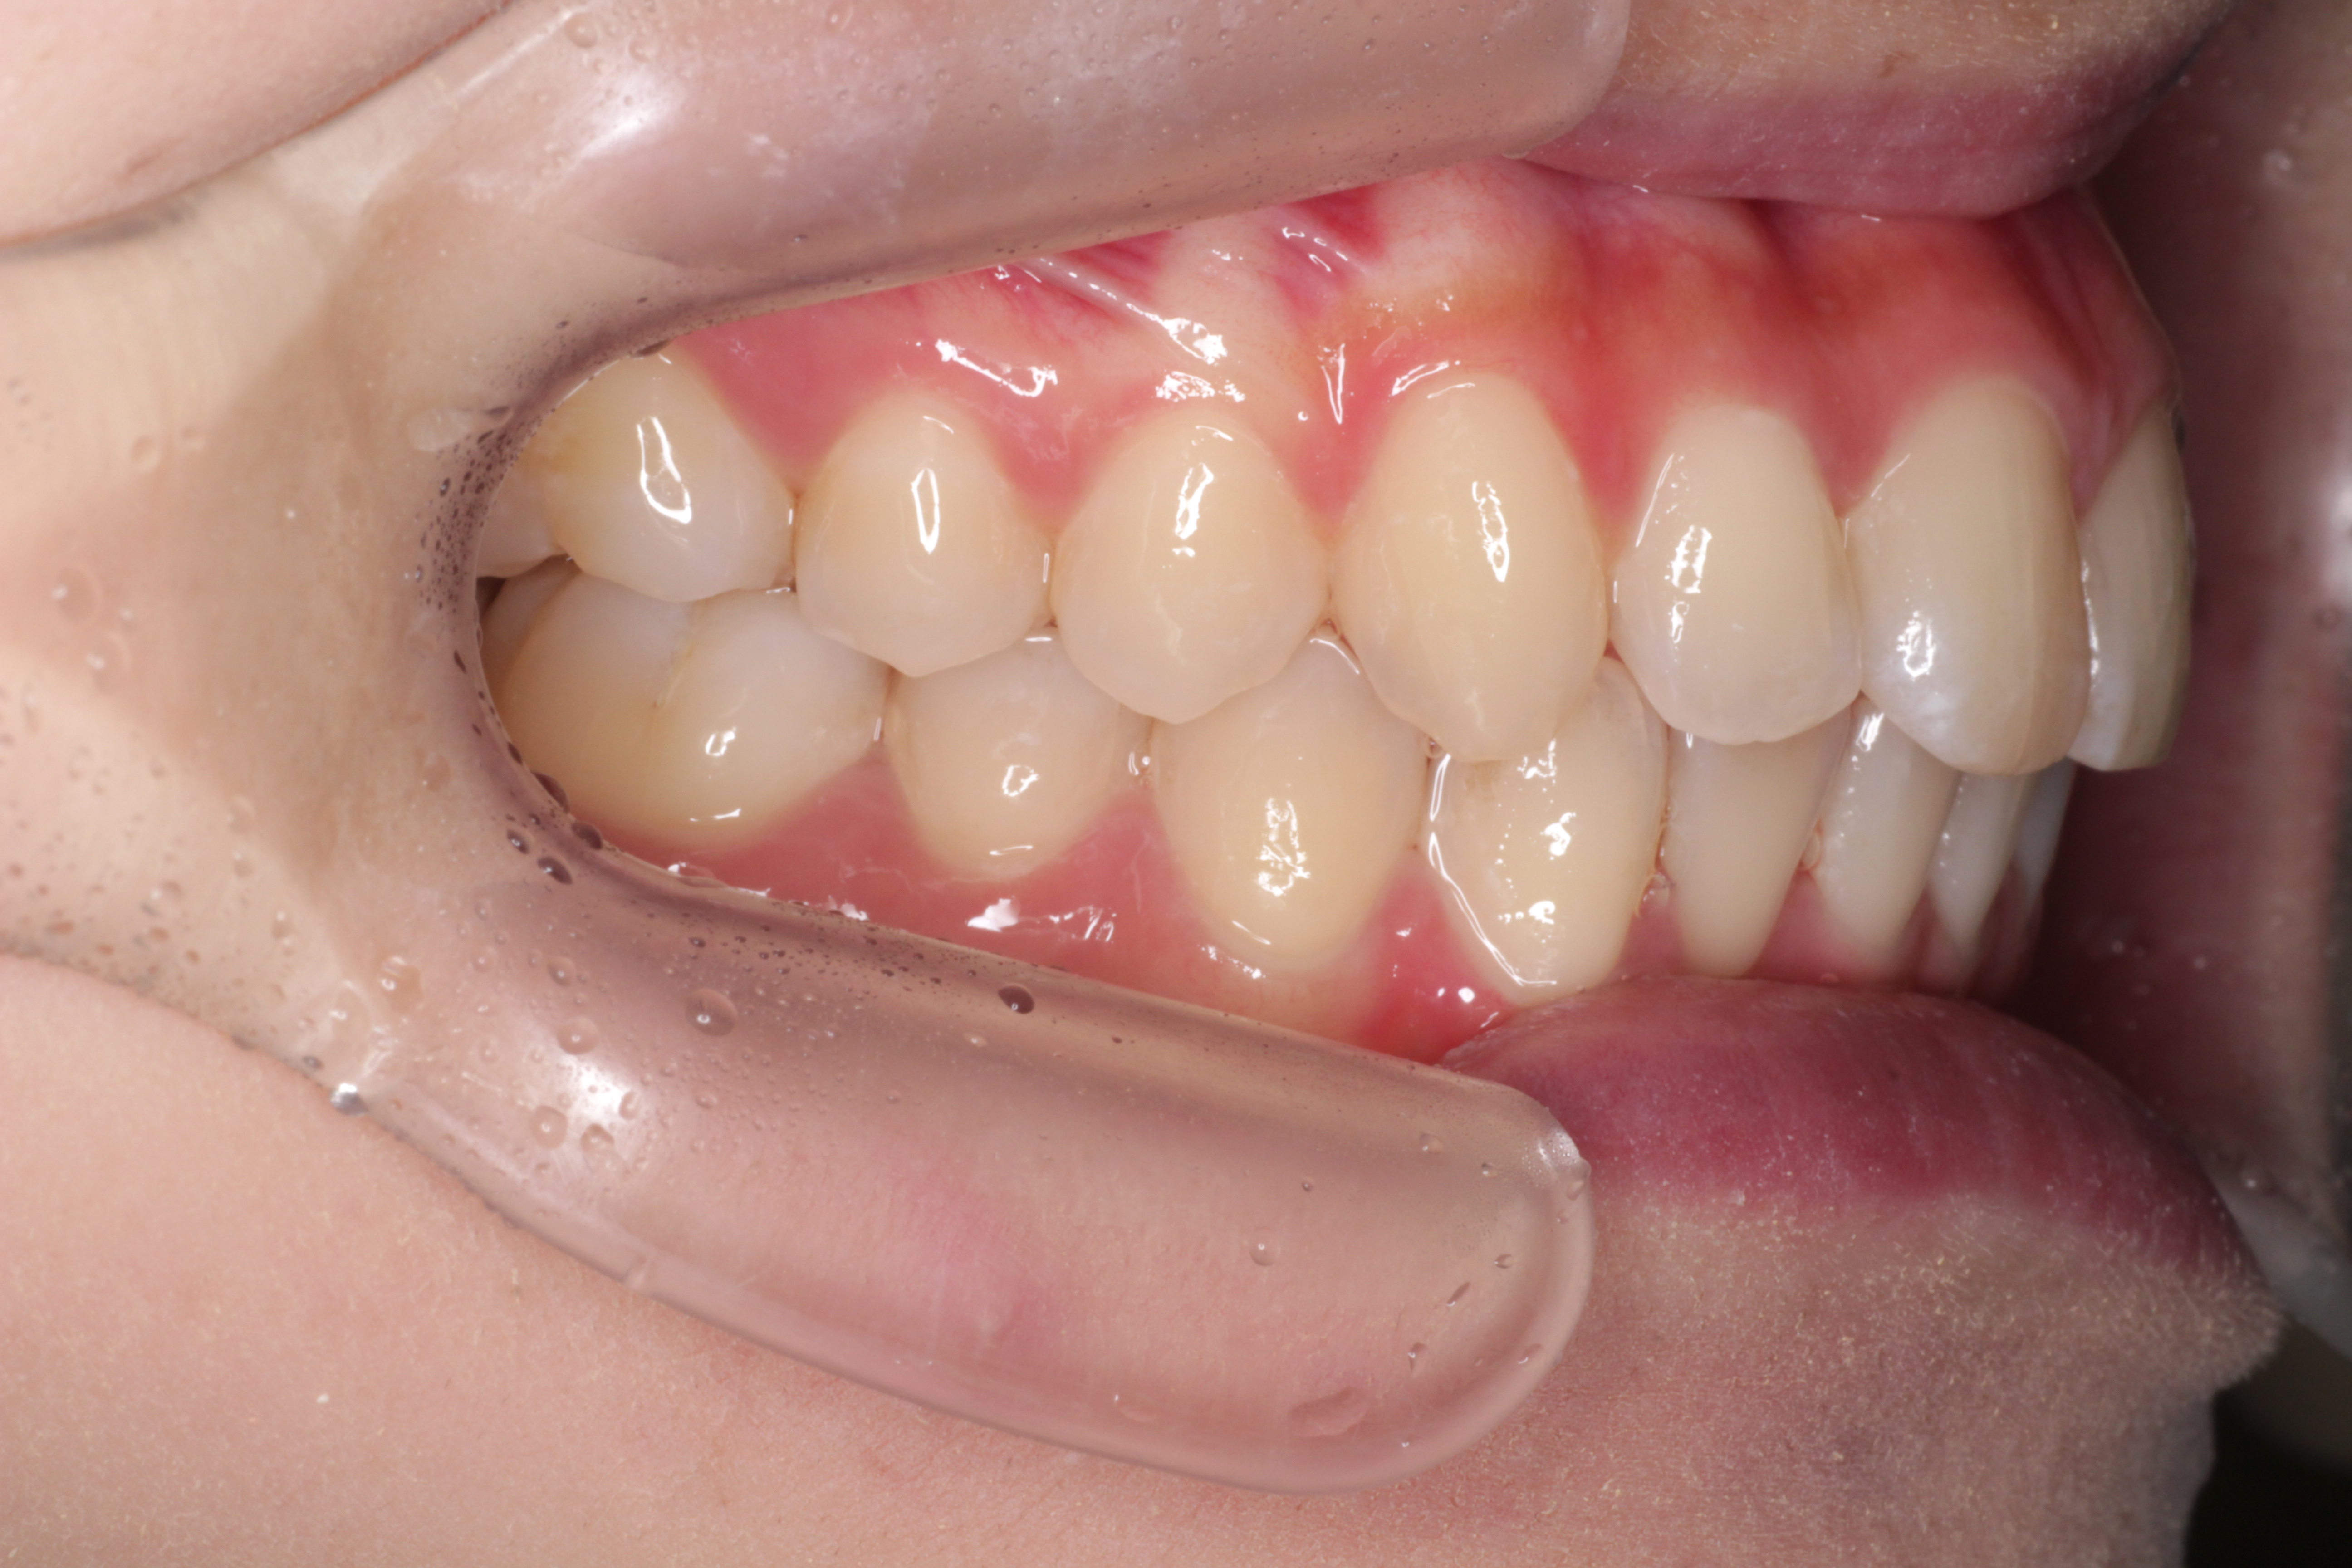

↓お口の中の状態です。

⑴深かった咬み合わせがしっかりと改善されました。

⑵右下の2番目の歯のずれも治りました。

⑶右上の2番目の歯の咬み合わせがよくなりました。

⑷正中も綺麗に合いました。

これで気になるところが改善されたので矯正は終了です。

これからは保定期間に入ります。